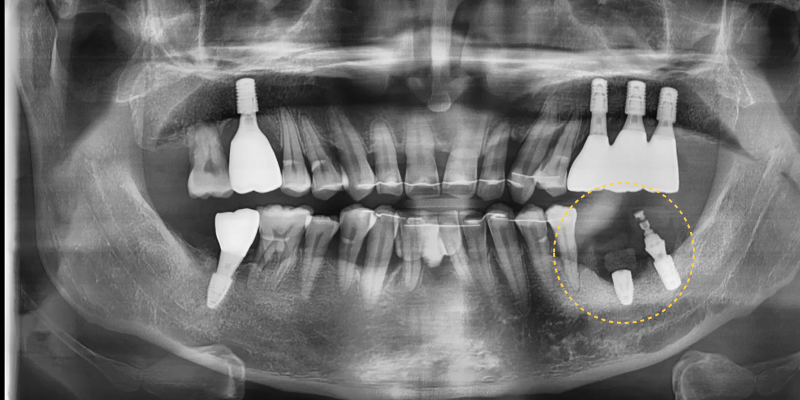

초진 파노라마 사진에서 만성 치주염으로 인해

치조골 소실이 매우 심한 상태가 확인되었습니다.

앞니부위는 교정을 하여 치아를 먼저 배열하고

어금니 부위는 발치 후 임플란트를 하기로 계획하였습니다.

그러나 앞니중에서도 치주가 너무 좋지않아

몹시 흔들리고 지지도 되지 않는

아래의 첫번째 앞니는 발치를 진행하였습니다.

전치부의 배열을 진행하면서

치조골의 파괴가 심각한 어금니 3개를 발치하고

임플란트를 식립하였습니다.